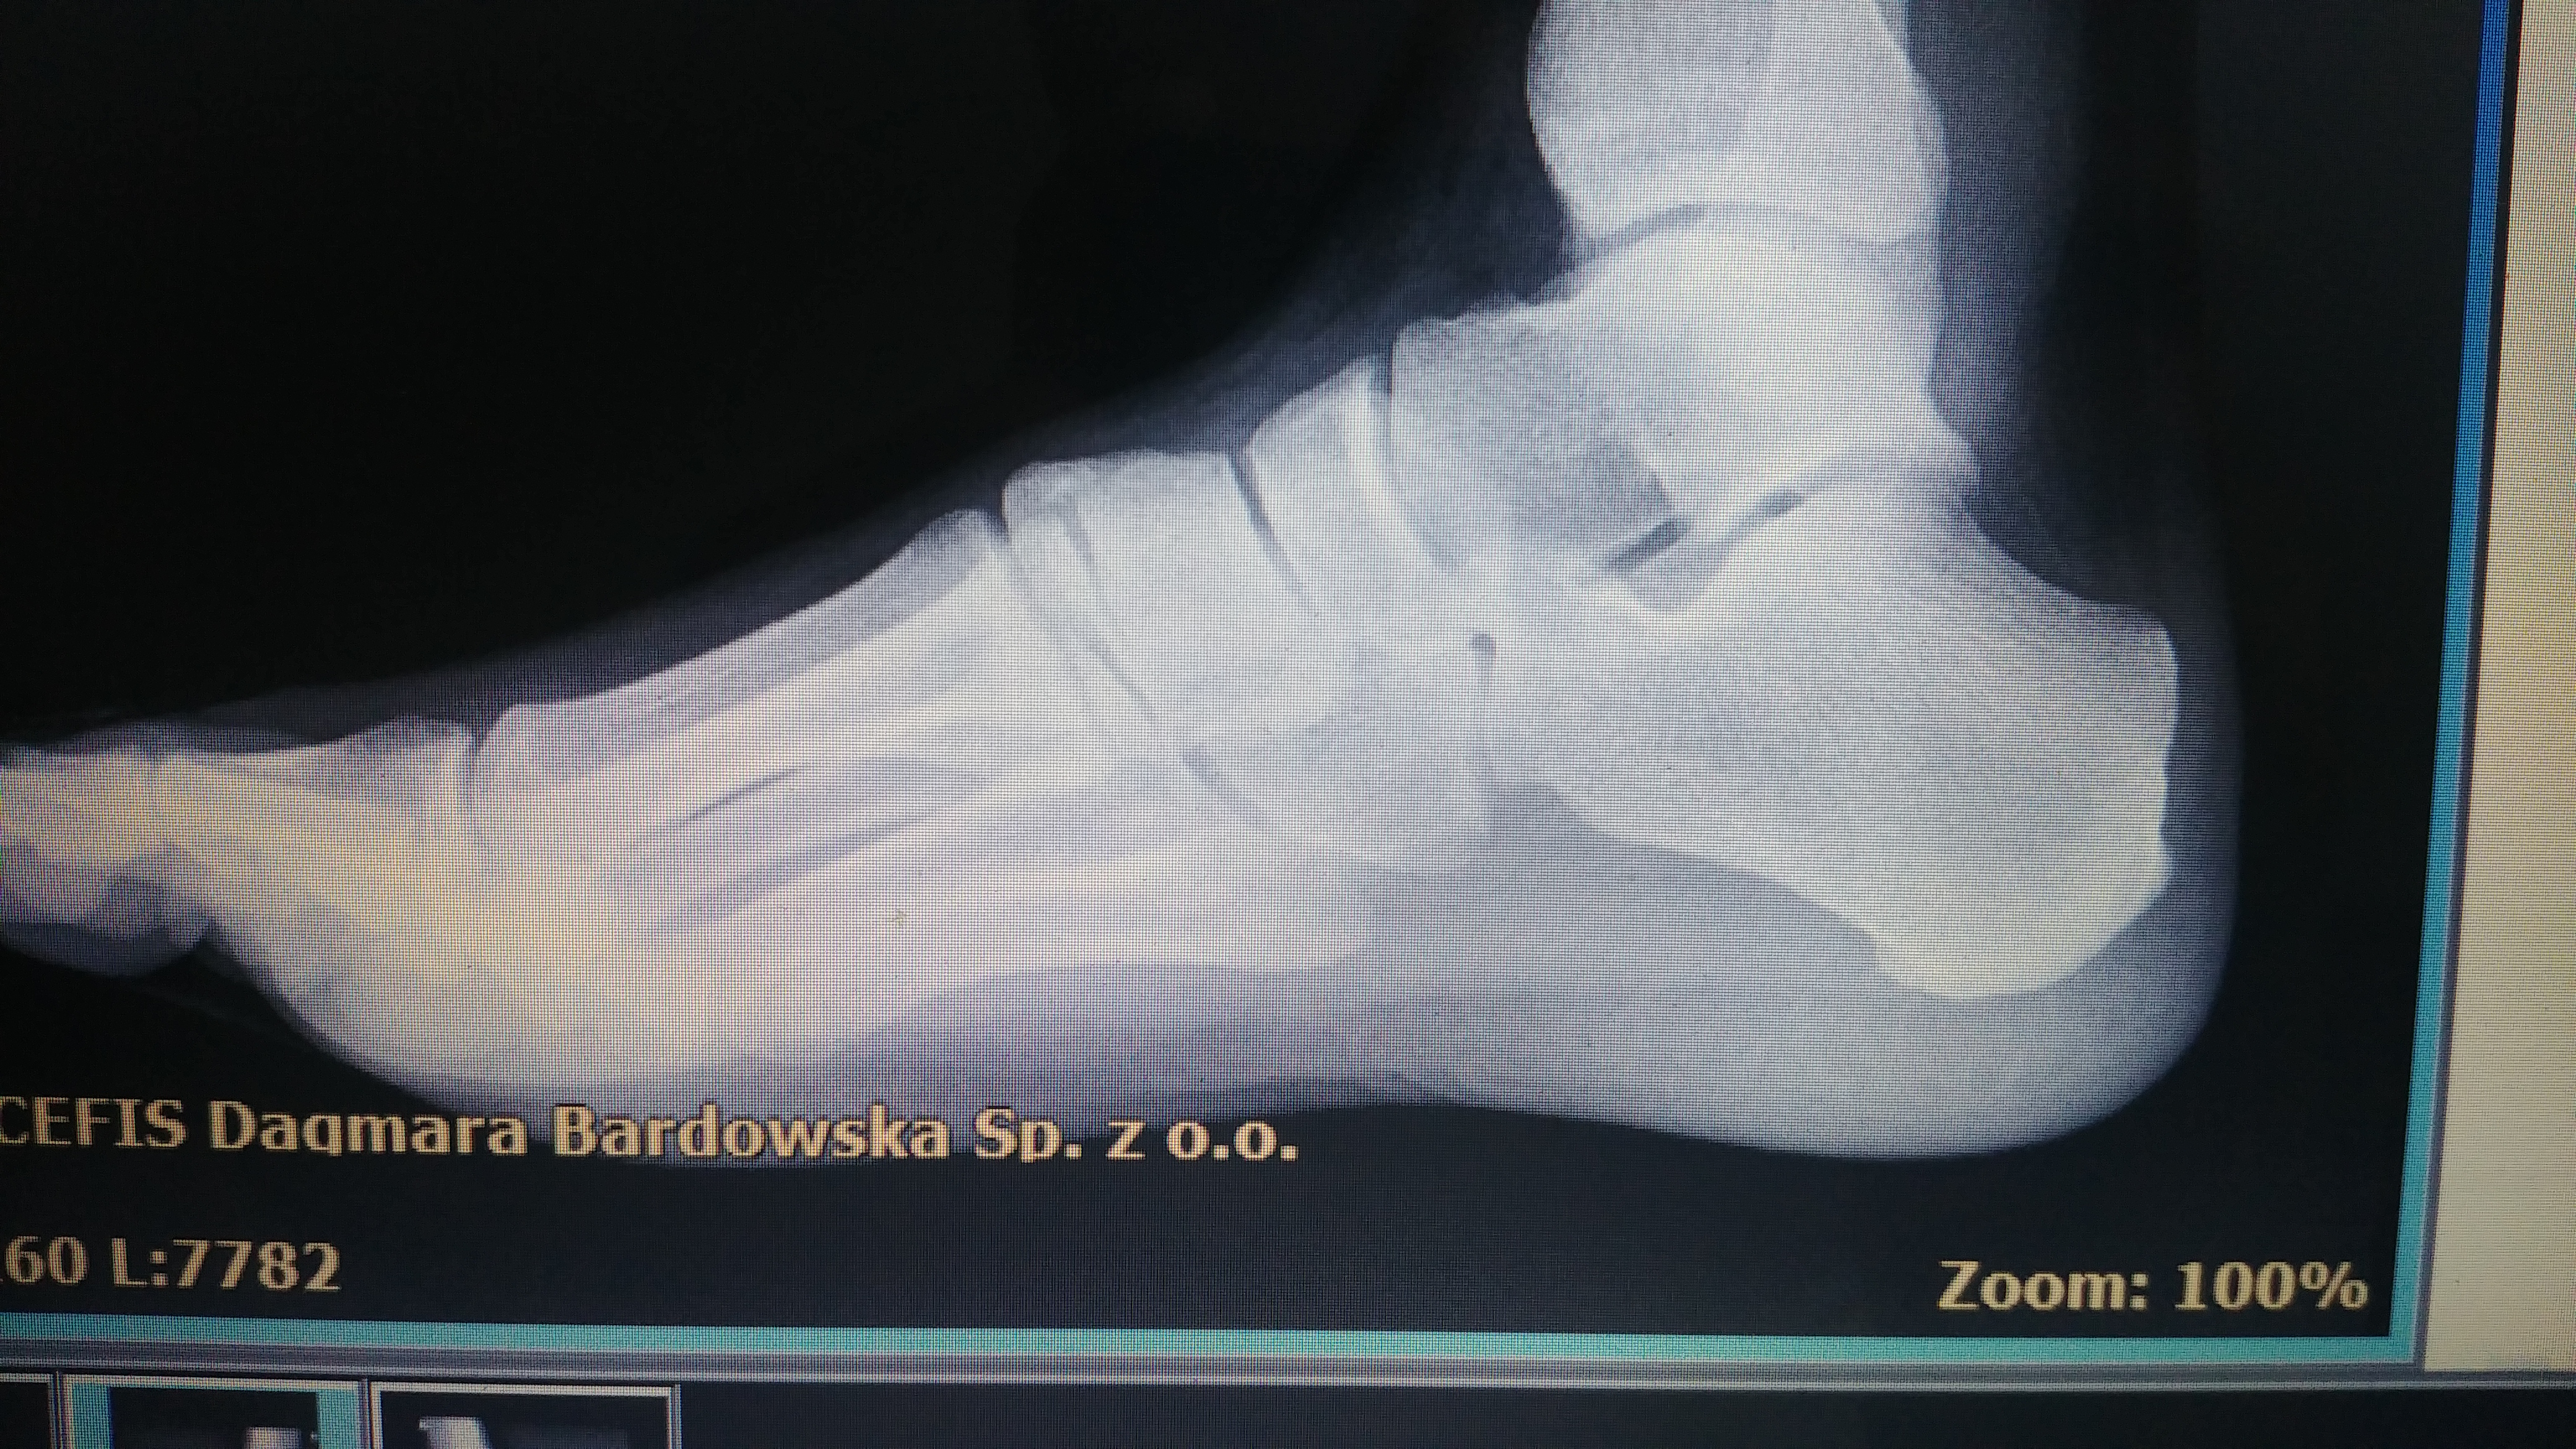

Witam. Od jakiegos roku mam problem z chodzeniem. Głownie problem występuje w prawej stopie. Podczas chodzenia mam uczucie jakby tylna górna część pięty cały czas ocierała i podrażniała moją pięte. W lewej stopie też występuje ten problem ale nie az w takim stopniu. Problem występuje tylko gdy noszę buty. Zrobiłem zdjęcia RTG na których nic nie wykazało zmian kostnych stopy. Później byłem u ortopedy i wyszło mu ze mam lekkie zapalenie ścięgna Achillesa. Ostatnio byłem u fizjoterapeuty i swierdził na podstawie zdjęc RTG ze niby ze stopami wszystko OK, ale nie podoba mu się stopa ze taka jakby była nadbudowana na dole ta część pięty. Zrobił masaż i szukał punktów spustowych czy jakos tak na ciele od których mógłby sie brac ten problem, następnie na tych piętach zrobił terapie falą uderzeniową i zalecił rozciąganie mięsni ( Ćwiczenia) na następne 3 miesiące i zobaczymy co to da. Ostatnio miałem też problem z łydkami. Strasznie się napinały głownie wieczorem i troche to bolalo. Próbowałem juz z 50 par butów i w 1 jest wiekszy problem a w drugich mniejszy z ta obcierająca pięta. Co dziwne buty które były dla mnie mega wygodne 2-3 lata temu, to teraz gdy w nich chodzę mam to uczucie obierania w nich głownie prawej stopy. Czasem jest tak ze jakby ten dyskonfort ustępuje i pare godzin jest OK. Nie mam juz pomysłów co to może być. Myśle zrobić pare zabiegów fali uderzeniowej i jeżeli jest to jakies zwapnienie na kości to powinno przyniesc jakies efekt. Jest jeszcze problem że podczas stania w 1 miejscu bolą mnie stopy od spodu. Mam 31 lat, mężczyzna.Proszę o pomoc.